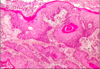

what strains of HPV causes genital warts and what does this look like histologically?

HPV 6 and 11

condyloma acuminatum = thickened “papillomatous” squamous epithelium with cytoplasmic vacuolation (koliocytosis)